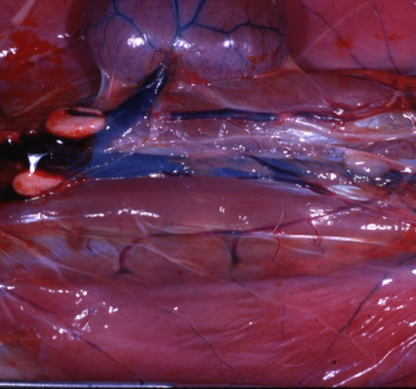

What can be seen here?

Ethylene glycol intoxication leading to Acute renal failure bright red and shiny medulla is bulging (indicative of presence of oedema)